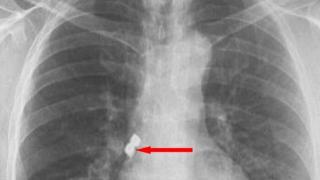

Implant dişlerini yuttu!

Bir kişinin diş tedavisi sırasında soluk borusuna kaçan iki implant müdahalenin ardından başarıyla alındı.